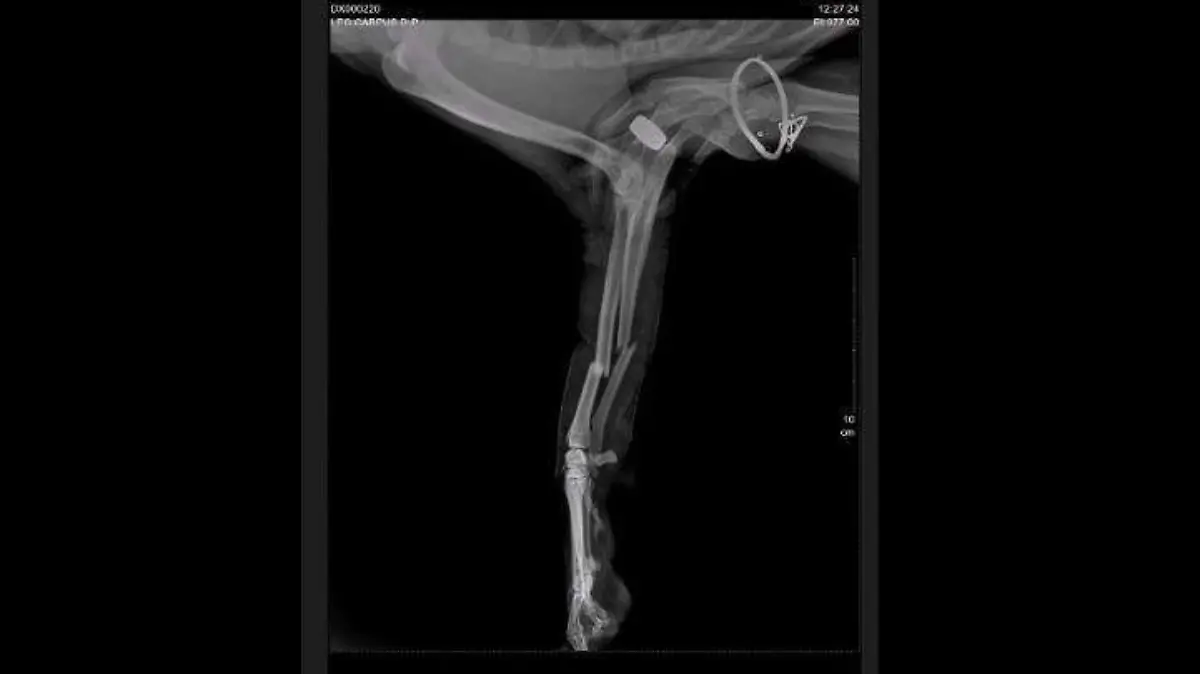

Un automovilista lo trasladó a una veterinaria ubicada en el municipio de Metepec para realizarle estudios; el canino presenta fractura de cúbito y radio por lo que necesita ser operado de urgencia